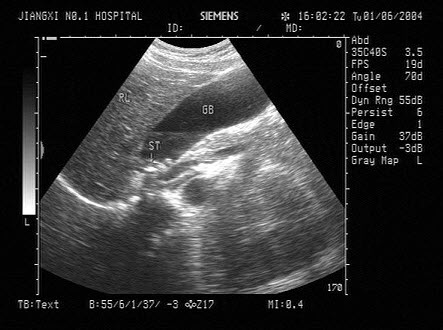

12、单项选择题

男,60岁,上腹疼痛不适数10年。结合超声声像图,诊断为()

A.胆囊多发性结石

B.胆囊多发性息肉

C.胆囊泥沙样结石

D.胆囊充满性结石并萎缩性胆囊炎

E.胆囊胆固醇结晶